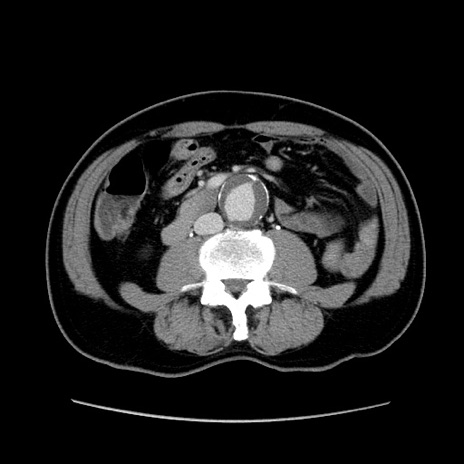

症例34(横断像)

【症例】60歳代 男性

【主訴】右鼠径部膨隆

【現病歴】1年程前より右鼠径部膨隆あり。自己にて還納可能だったため放置していた。3時間前より右鼠径部の脱出を認め、還納困難となり受診。

【身体所見】右鼠径部に小児頭大の膨隆あり。弾性硬であり、用手還納は困難。左鼠径部にも膨隆を認める。脱出はなし。